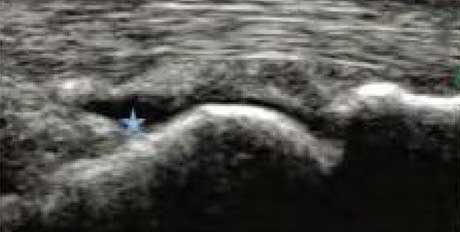

• 肌骨超声判定RA病情处于发展、活跃期

患者双手中指、无名指关节晨僵、疼痛半年,通过肌骨超声检查发现关节滑膜组织厚度3.62mm,周边血流增多,呈较多点状血流信号,判定RA处于快速发展、活动期。